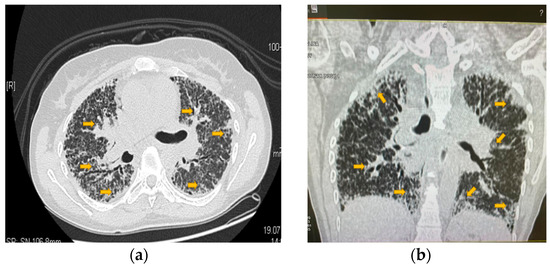

5. Evidence-Based Assessment of a Patient with RA and LAM